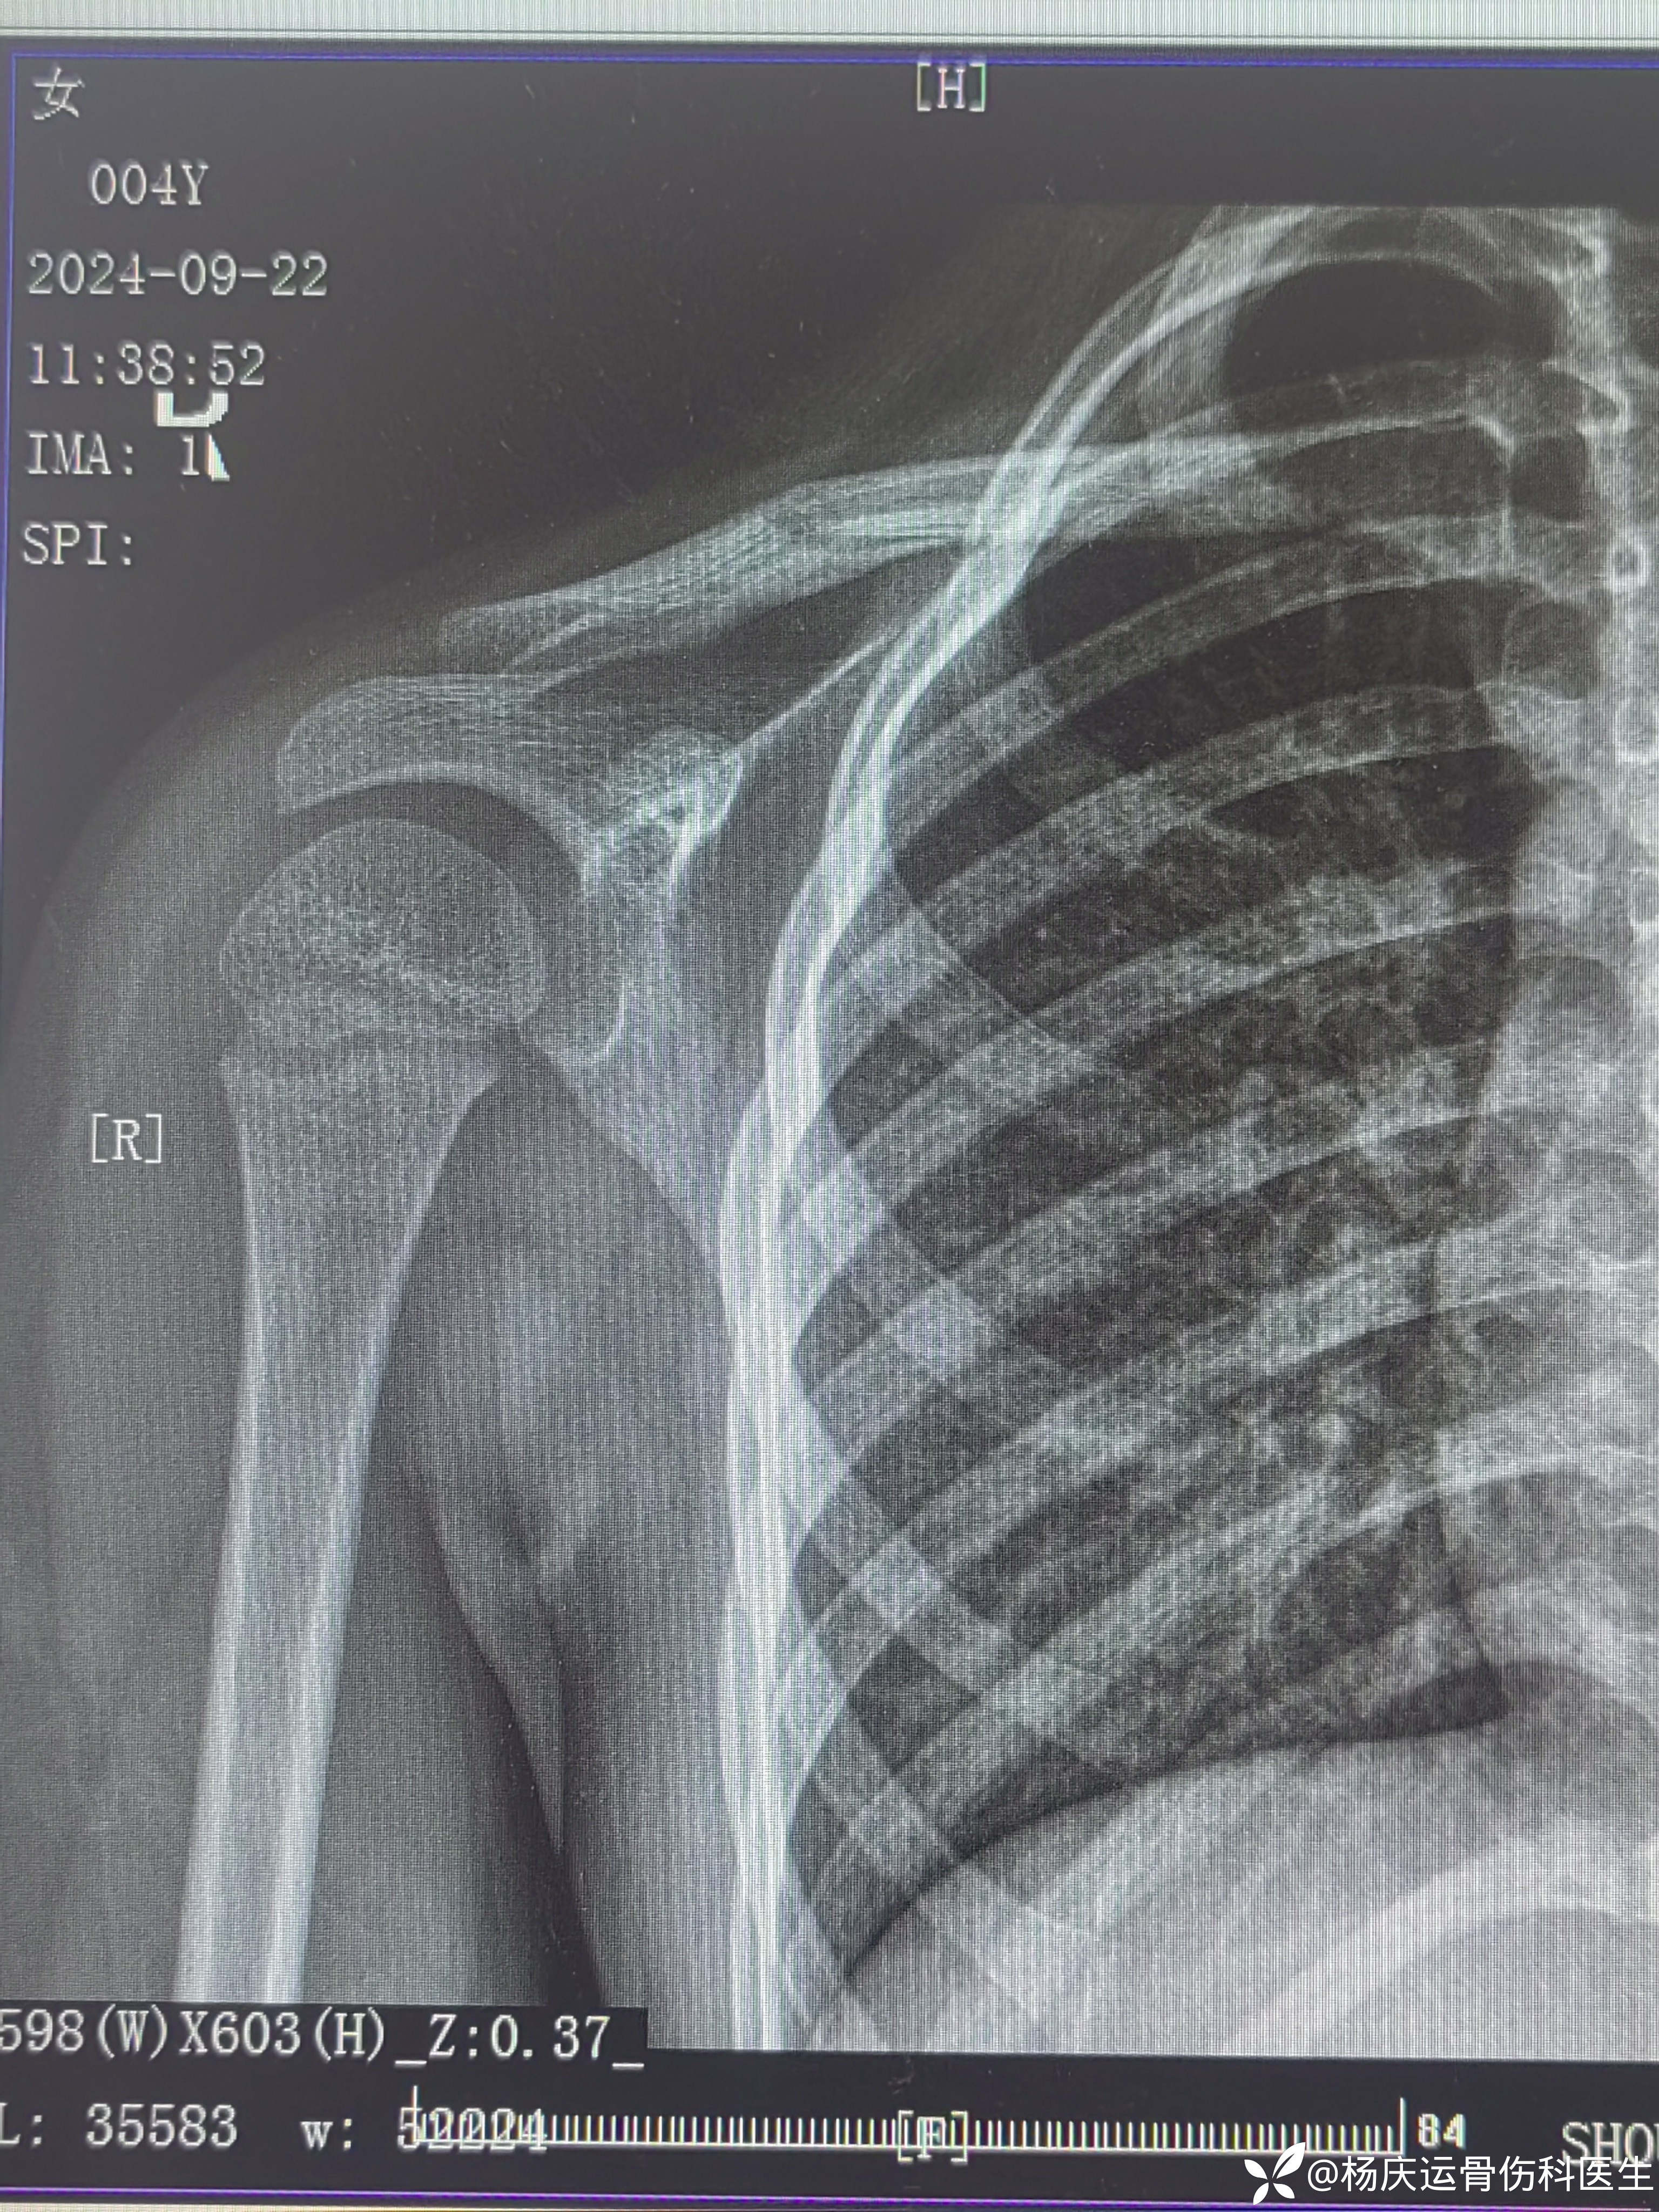

患者万,女,4岁,右肩外伤肿痛畸形活动受限2小时。

8字绷带外固定后,患者有明显的不适感,且家属对骨折位置不满意。